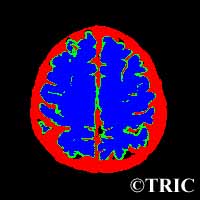

mri.jpg脳のMRI画像解析

Copyright(C)TRIC